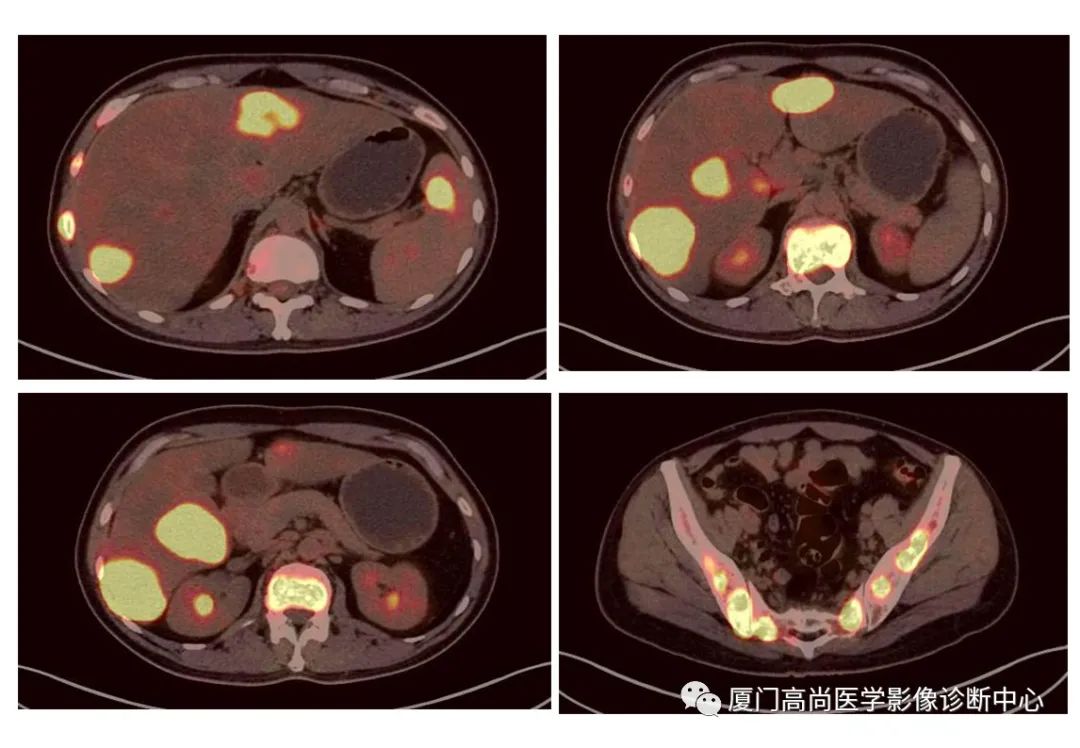

病例2、某女士,62歲,近3個(gè)月來自覺消瘦,無其他自覺癥狀,CT發(fā)現(xiàn)雙側(cè)腎上腺增大,性質(zhì)待定,查血各項(xiàng)腫瘤標(biāo)記物均正常,臨床診斷不清,申請(qǐng)做PET/CT檢查

左心房淋巴瘤病灶

右心房淋巴瘤病灶

雙側(cè)腎上腺病灶、膽囊病灶

腹腔淋巴結(jié)腫大

小腸多段淋巴瘤病灶

PET/CT發(fā)現(xiàn) :左心房、右心房見團(tuán)塊狀FDG攝取增高;雙側(cè)腎上腺增大,F(xiàn)DG攝取增高;膽囊和胃壁結(jié)節(jié)樣FDG攝取增高;小腸多節(jié)段腸壁增厚,F(xiàn)DG攝取增高;腹膜后、腹腔及盆腔多發(fā)淋巴結(jié)腫大,F(xiàn)DG攝取增高;上述考慮為淋巴瘤

經(jīng)腎上腺穿刺活檢 :病理證實(shí)為彌漫大B細(xì)胞淋巴瘤